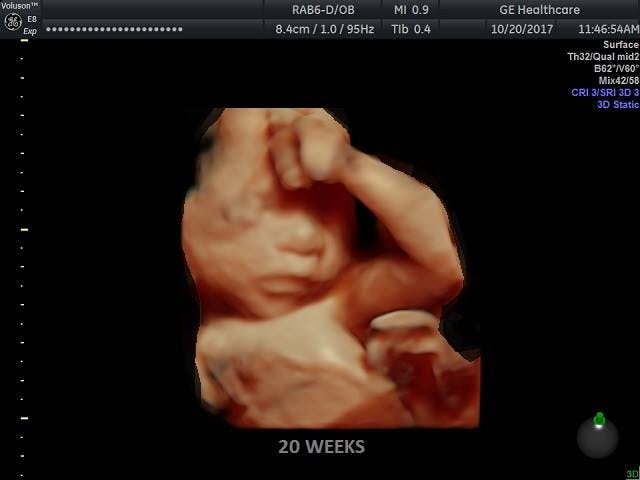

First, Allen attacks it for suggesting that babies are capable of feeling pain by 20 weeks, which she claims “directly contradicts current scientific consensus.” The American College of Obstetricians and Gynecologists even told Texas that fetal pain was “ideological rather than scientific”!